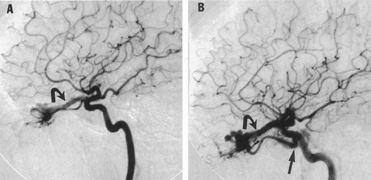

Of particular interest are those AVMs that involve the occipital lobe (Fig. 9). The clinical differentiation of migraine from a cerebral AVM was previously regarded as difficult because the clinical features of occipital lobe AVMs include visual phenomena or headaches. However, in most cases the clinical distinction is possible. In 26 cases with occipital AVM, two distinct syndromes were defined in 18 patients: occipital epilepsy and occipital apoplexy.73 Focal seizures with occipital malformations consist of elementary visual sensations similar to the phenomena evoked by direct cortical stimulations. When seizure activity occurs in the striate cortex (area 17), the patient usually reports sensations of moving lights in the right or left homonymous fields. The sensations are poorly formed, episodic, usually brief, sometimes colored, and unassociated with the angular, scintillating figures so characteristic of migrainous cortical phenomena. Epileptic discharges from areas 18 and 19 cause photopsias that are unlikely to remain stationary and to flicker rapidly. The epileptic photopsias usually last only seconds; occasionally they last for a few minutes before the onset of a generalized seizure. In other instances only the brief visual episodes occur without spreading to produce a generalized seizure. Momentary dimming or blindness in one or both homonymous fields may be experienced with seizure activity in the occipital areas.

Fig. 9. Carotid arteriogram of an occipital lobe arteriovenous malformation (AVM). Lateral (A) and frontal (B) projections demonstrating a small occipital AVM (arrow). The patient was a 23-year-old woman who presented with severe apoplectic unilateral headache, total left homonymous hemianopia, and mild nuchal rigidity. Despite xanthochromic cerebrospinal fluid, she was initially diagnosed elsewhere as having migraine. An AVM was successfully resected, and a small occipital lobe hematoma was removed.

Occipital apoplexy results from hemorrhage and hematoma formation within the occipital lobe and is characterized by sudden severe headache and homonymous visual field loss. Homonymous hemianopia is the most important sign produced by vascular malformations of the occipital lobe. Compression and necrosis of visual pathways by an intracerebral hematoma are the principal mechanisms. Usually the hematoma is large and tends to split or dissect longitudinally through the white matter of the occipital lobe. The effects of compression may be reversed by prompt, surgical evacuation of the hematoma.73 With hemorrhage into one occipital lobe, hemianopia in the visual field of the contralateral normal occipital lobe may develop, producing total blindness that can last for several days. The rapidly expanding hematoma may shift the damaged hemisphere anteriorly, or across the midline, with downward herniation of the uncus through the tentorial incisura. This shift compresses the posterior cerebral arteries and accounts for bilateral occipital lobe dysfunction. Arrest of function in the undamaged occipital lobe may be due to an interhemispheral inhibitory phenomenon termed diaschisis. Visual field defects with occipital AVMs are regularly due to hemorrhage and hematoma formation. Congenital arteriovenous malformations can occupy the entire occipital pole (the macular projection area) for decades without producing visual field defects.

Although migraine is often cited as a symptom of AVM, it is extremely rare that classic migraine is mimicked by occipital AVM. None of the patients in the series by Troost et al73 described the 15- to 20-minute episodes that characterize the visual aura of classic migraine. The headaches of AVM differ from migraine in that they are constantly localized to the same side of the head, and intermittent visual phenomena, if present, can persist throughout the headache or even after, whereas in migraine the visual phenomena usually precede the headache. Bruyn74 has reviewed the clinical features of 57 reported and 7 personal cases of AVM, concluding that the migraine of AVM is late onset, nonfamilial, and brief. Rarely, the complete clinical symptomatology of classic migraine can be mimicked by an occipital lobe AVM (see Chapter 16).75 In addition to hemianopia, other visual disturbances can occur after hemorrhage into the occipital lobe, including alexia without agraphia (see Chapter 7).